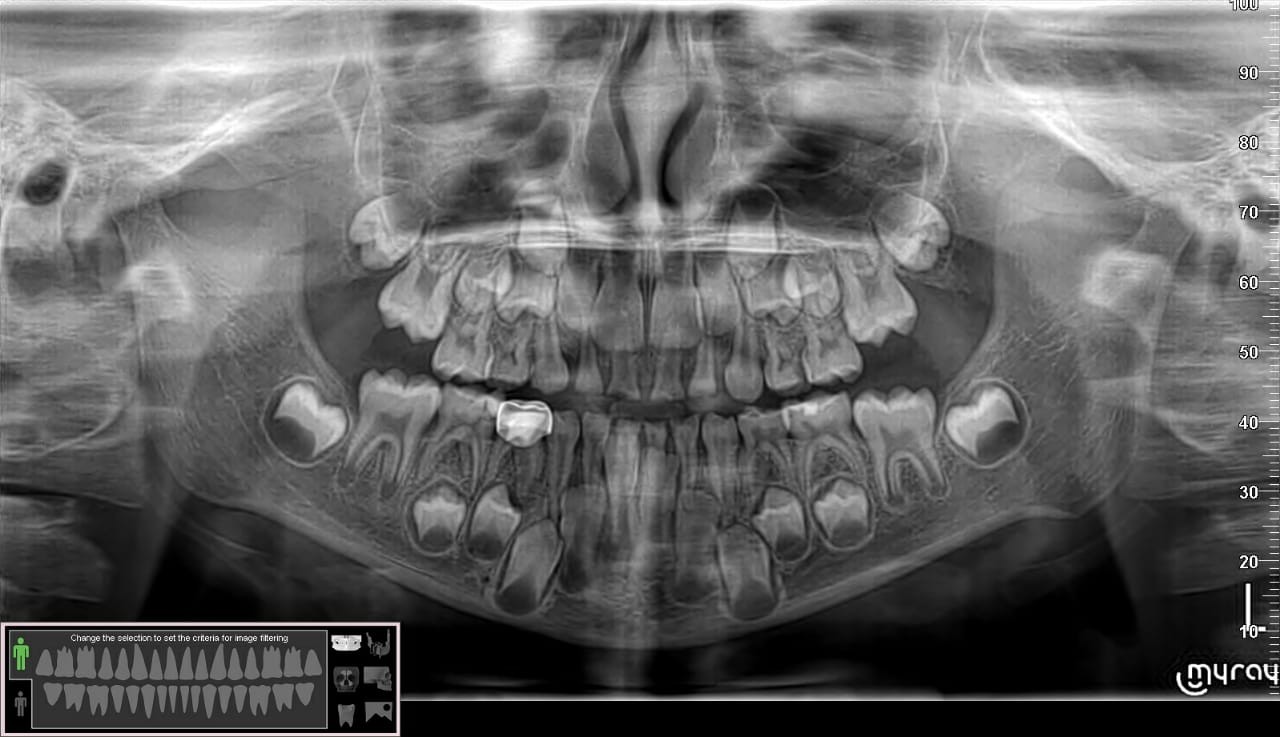

حشو الأطفال هو هو إجراء طبي يهدف إلى معالجة تلف السن الناتج عن التسوس، ويتم الحشو عن طريق إزالة الجزء المتضرر من السن، وملء التجويف المتسبب بهذا التلف باستخدام مواد طبية خاصة تساهم في استعادة وظيفة السن و مظهره الجمالي.

الحشو الأطفال هو إجراء طبي يهدف إلى علاج تسوس الأسنان واستعادة الأسنان المتضررة إلى حالتها الطبيعية، وهناك عدة مميزات للحشو عند الأطفال تجعلها مهمة وضرورية، ومنها: